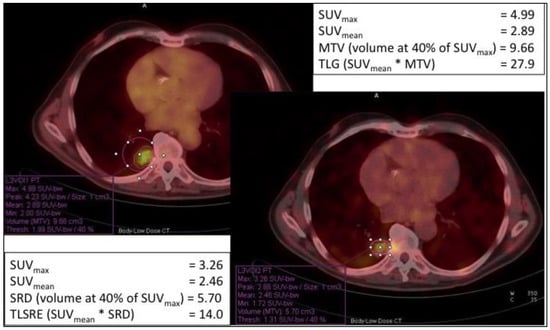

- Chan, D.L.H.; Pavlakis, N.; Schembri, G.P.; Bernard, E.J.; Hsiao, E.; Hayes, A.; Barnes, T.; Diakos, C.; Khasraw, M.; Samra, J.; et al. Dual Somatostatin Receptor/FDG PET/CT Imaging in Metastatic Neuroendocrine Tumours: Proposal for a Novel Grading Scheme with Prognostic Significance. Theranostics 2017, 7, 1149–1158. [Google Scholar] [CrossRef]

- Abdulrezzak, U.; Kurt, Y.K.; Kula, M.; Tutus, A. Combined imaging with 68Ga-DOTA-TATE and 18F-FDG PET/CT on the basis of volumetric parameters in neuroendocrine tumors. Nucl. Med. Commun. 2016, 37, 874–881. [Google Scholar] [CrossRef]